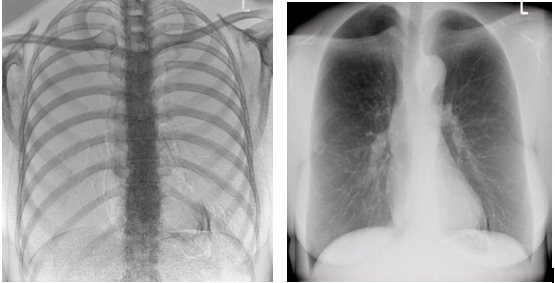

1)大視野無遺漏

17*17英寸的高清像素動態平板探測器,能對胸部、腹部等部位實現大范圍全覆蓋,動靜態之間無感切換。透視檢查無須對患者重新定位便可觀察到足夠大的人體器官組織,避免漏診誤診。更好地減少了曝光時間,也減少了病人的輻射劑量。

大尺寸動態平板技術,覆蓋檢查面積范圍廣,輕松實現胃十二指腸等大面積造影,無需移動即可觀看整個動態過程,避免噪點對圖像的影響。

2)圖像質量無畸變,無失真

高效動態平板技術,圖像不會有幾何畸變,提供高分辨率和精確的圖像,為臨床診斷提供精準依據。